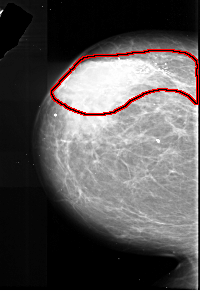

FILE: A_1017_1.LEFT_MLO.OVERLAY

TOTAL_ABNORMALITIES 1

ABNORMALITY 1

LESION_TYPE CALCIFICATION TYPE PLEOMORPHIC DISTRIBUTION SEGMENTAL

ASSESSMENT 5

SUBTLETY 5

PATHOLOGY MALIGNANT

TOTAL_OUTLINES 1

BOUNDARY